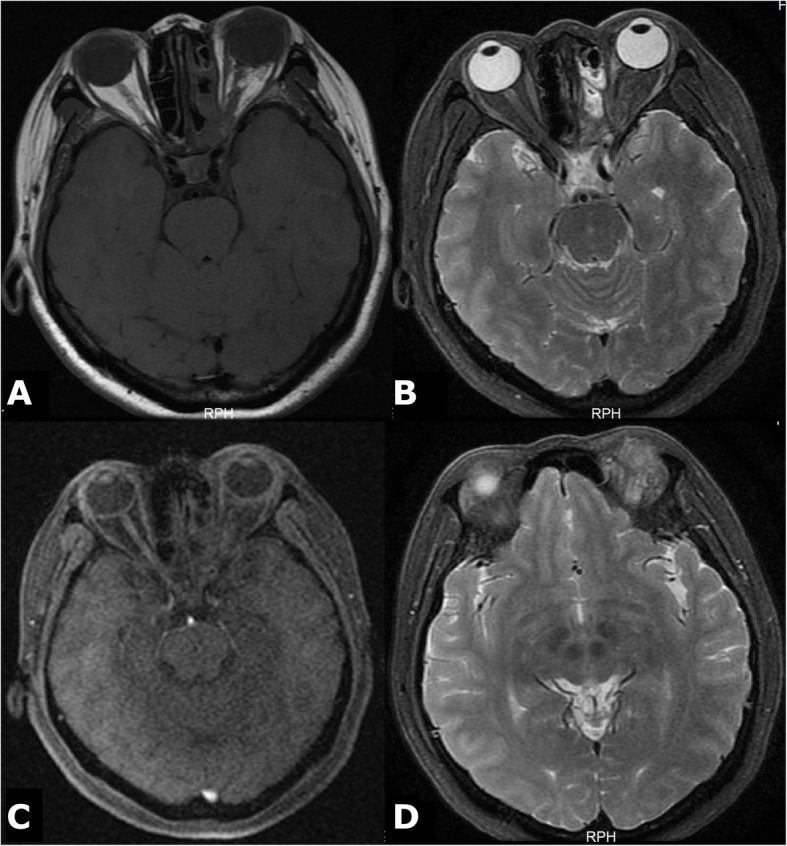

Magnetic resonance imaging (MRI) showed a mass at the back of the left orbital optic nerve, with isointensity on T1 and hyperintensity on T2/fluid-attenuated inversion recovery (FLAIR) imaging. Heterogeneous enhancement was found on a contrast-enhanced scan (Fig. 1: a, b, c, d). There was no obvious flow void in or around the tumour. The proximal end of the optic nerve on the left side of the orbit was partially enlarged and tortuous, and the optic nerve sheath was dilated. There was no obvious abnormality in the right optic nerve. FLAIR imaging showed hyperintensity of the chiasma, left optic tract, and bilateral frontal lobes (Fig. 1: e, f, g).

Fig. 1.

Comparison of preoperative and postoperative MRI. The T1- and T2-weighted images show optic neuropathy before the operation. The T1 image shows isointensity (a), and the T2 and FLAIR images show hyperintensity (b, c). There was a significantly enhanced signal in the tumour after the enhancement scan (d). The FLAIR image shows hyperintensity of the left optic chiasma, visual radiation, and bilateral frontal lobe (e, f, g)